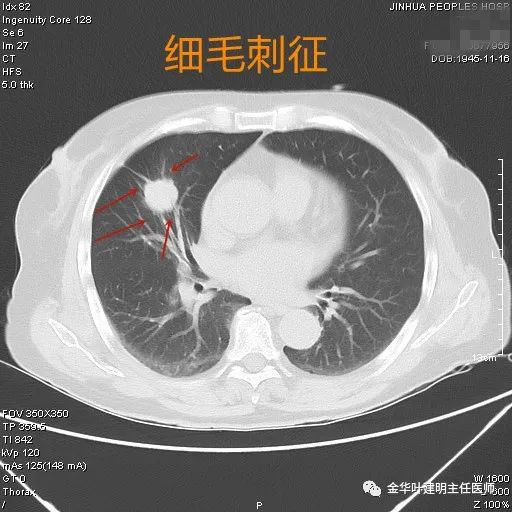

关于胰腺实性假乳头状肿瘤的特征,这病年轻人尤其女性更容易中招,平均年龄33岁左右。症状嘛,典型表现就是腹痛,但确实没啥特异性。CT检查会显示边界清晰的囊实性肿块,实性部分会慢慢强化,有时还能看到钙化点。